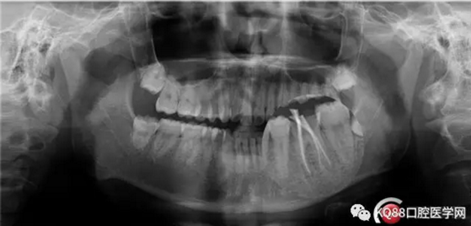

一周后復(fù)診,無明顯不適。擬樁,全冠修復(fù)。

12.png

首先預(yù)備樁道,樁道預(yù)備完成,用樹脂封閉根管口。嵌入兩根纖維樁。樁核粘結(jié)劑做基。

13.png

3M樹脂修復(fù)缺損。舌側(cè)電刀切齦,暴露齦壁,修整,制備。單線排齦,取模。

下次戴上全鋯全冠,整個(gè)治療修復(fù)過程就完成了。